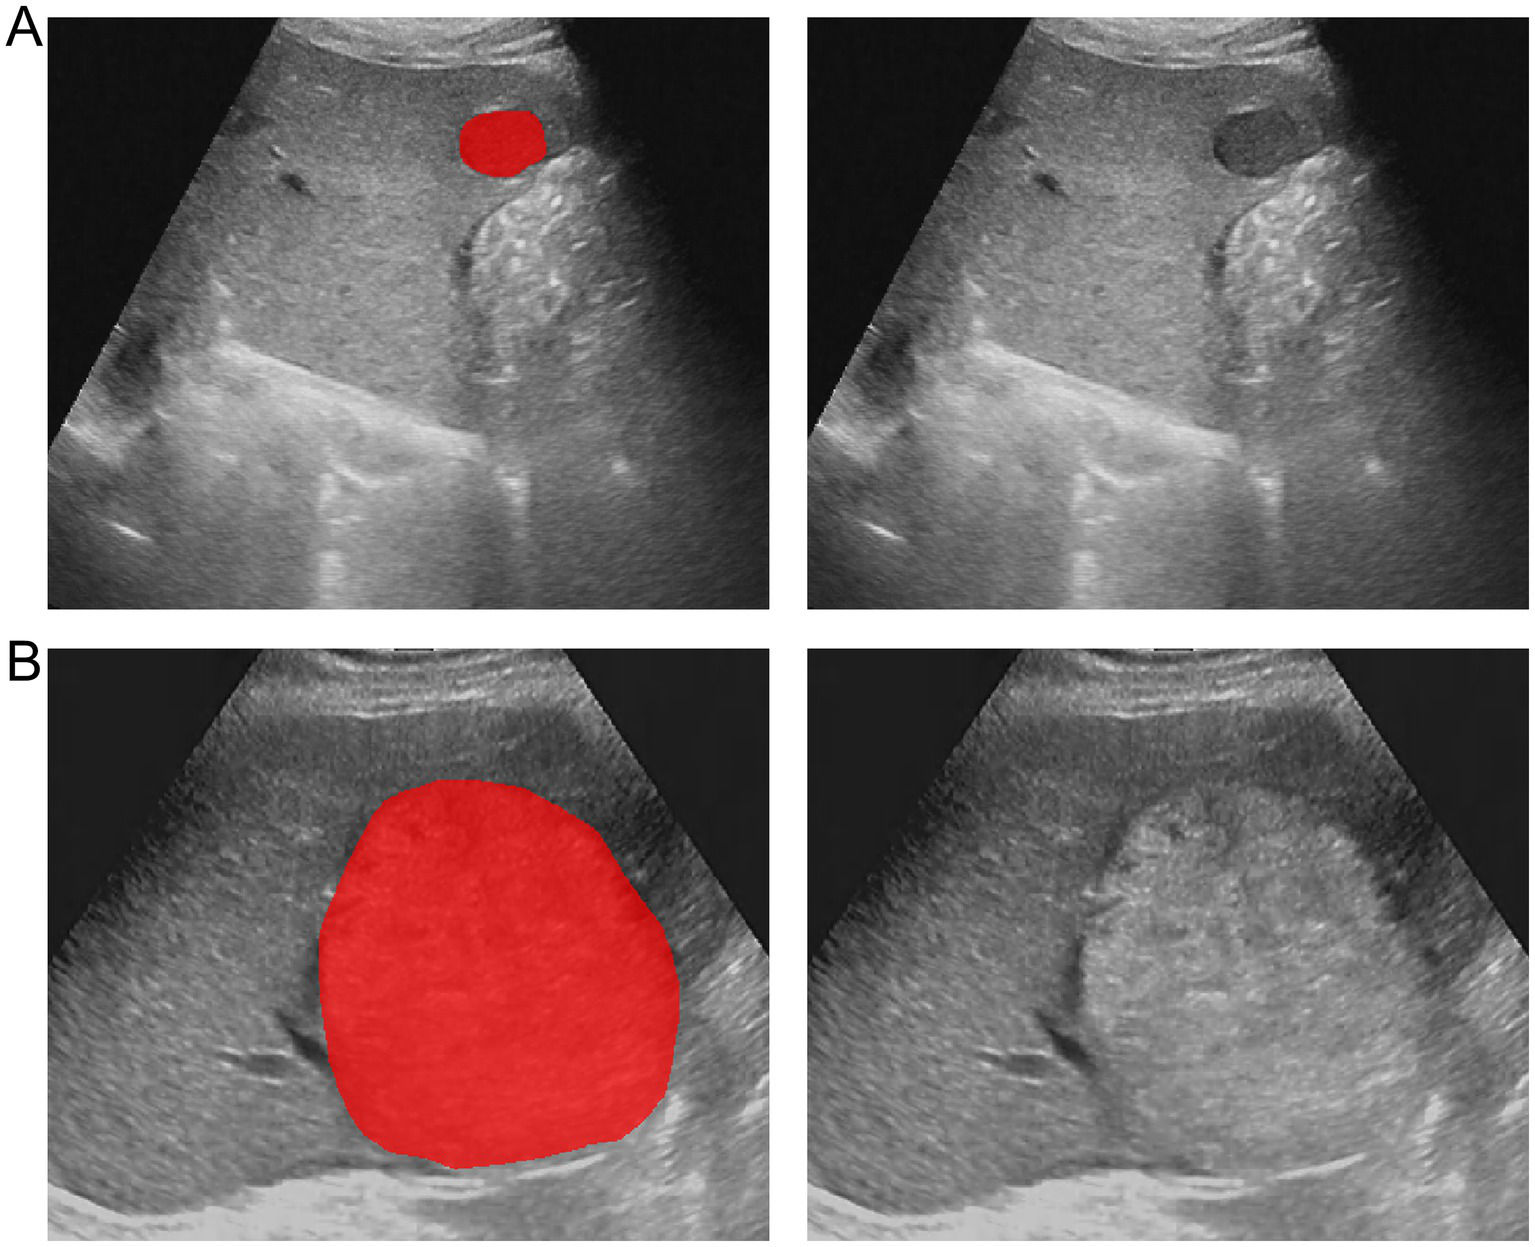

The region of interest (ROI) of the HCC lesions was manually segmented using ITK-SNAP software (version 3.8.0) (38). The ROIs of all lesions were manually delineated by a radiologist along the tumor margin. To assess the reproducibility of the features, 30 HCC lesions were randomly selected and their ROIs were independently delineated by another radiologist. Both radiologists were blinded to the clinical and pathological information of the patients. The intraclass correlation coefficient (ICC) was calculated to assess the reproducibility of the features. An ICC value closer to 1 indicates higher reliability. Only features with an ICC value of ≥ 0.80 were included in the subsequent feature selection. Figure 2 illustrates the representative segmentation results of the HCC lesions.

Figure 2

Example of delineating region of interest (ROI) on grayscale ultrasound images. (A) The lesion segmentation image and original image of a patient with wild-type TP53. (B) The lesion segmentation image and original image of a patient with mutant TP53.